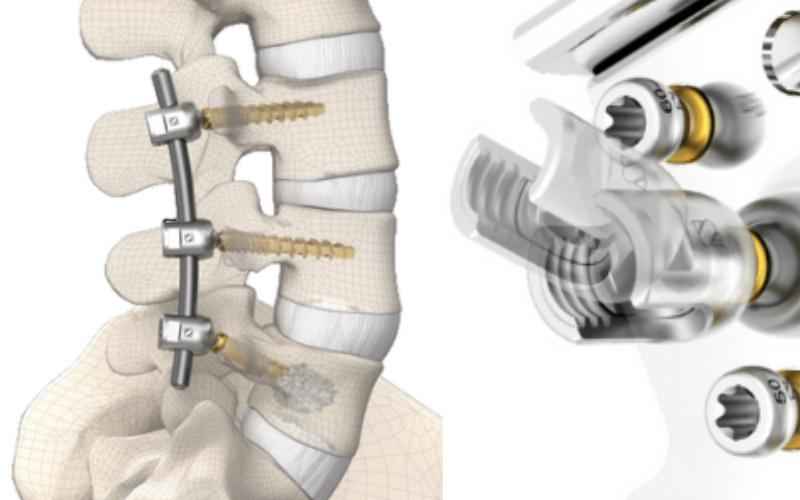

El Sistema de Columna Transpedicular ofrece una solución confiable para la estabilización y corrección de patologías vertebrales. Diseñado con tecnología de alta precisión y materiales biocompatibles, proporciona una fijación segura, adaptabilidad anatómica y soporte óptimo durante el proceso de recuperación, garantizando resultados quirúrgicos eficientes y duraderos.